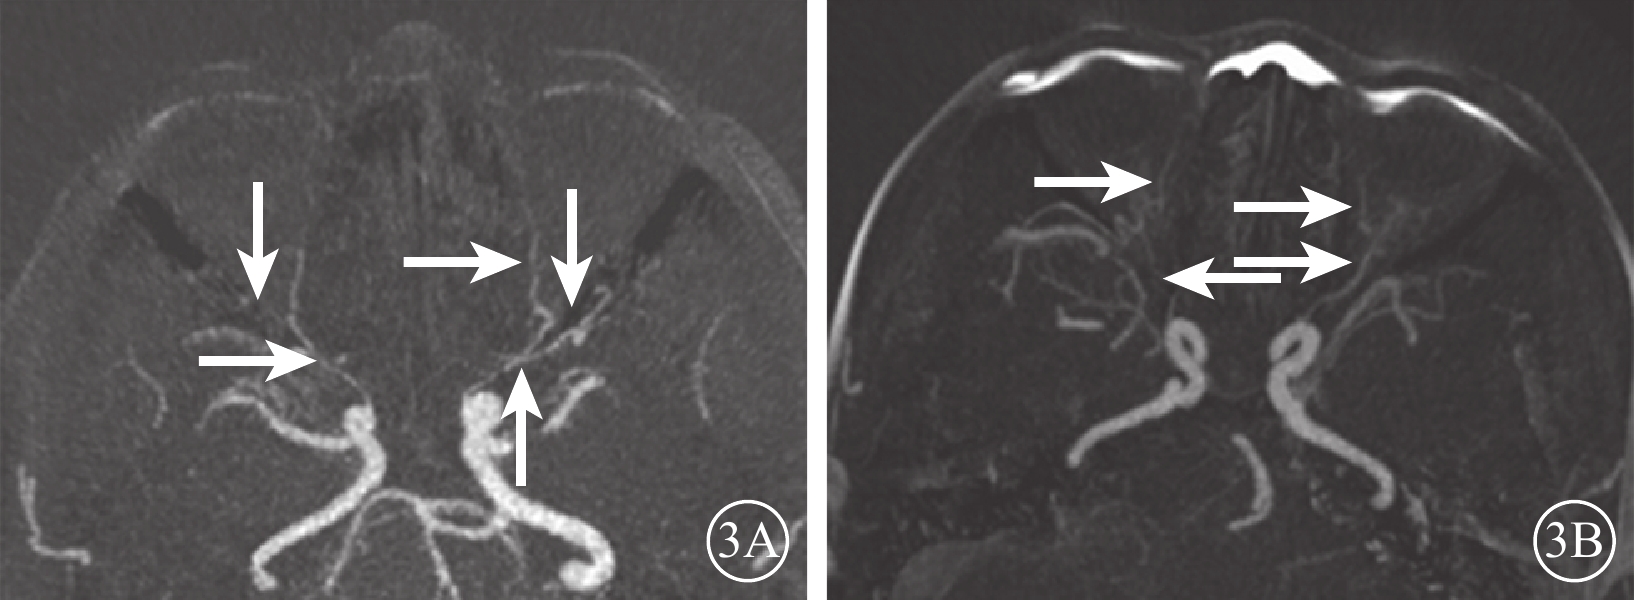

DR組72只眼中,眼動脈MRA 0級28只眼(38.9%);Ⅰ級28只眼(38.9%),其中眼動脈主干及其主要分支(鼻背動脈和淚腺動脈)顯影淺淡、外形變硬(圖2A)12只眼,眼動脈主干顯影正常、分支顯影中斷或不顯影14只眼;Ⅱ級16只眼(22.2%),其中眼動脈狹窄、僵硬伴分支顯影淺淡10只眼,分支顯影中斷或不顯影(圖2B)4只眼,眼動脈主干及其主要分支均不顯影2只眼。行CTA檢查的24只眼中,0級13只眼;Ⅰ級6只眼,其中眼動脈主干及其主要分支(鼻背動脈和淚腺動脈)顯影淺淡、管壁變硬(圖3A)4只眼,眼動脈主干顯影正常、分支不顯影2只眼;Ⅱ級5只眼,其中眼動脈主干伴分支明顯狹窄、僵硬(圖3B)3只眼,表現為眼動脈主干顯影分支不顯影2只眼。DR組眼動脈MRA、CTA分級一致性分析,Kappa值=0.86,一致性極強(表1)。DR組眼動脈MRA與對照組眼動脈MRA不同分級眼數比較,差異有統計學意義(Z=?5.74,P=0.000)。

圖3

DR患者CTA像。3A、3B. 分別為圖2A、2B患者CTA像。影像表現同MRA

圖3

DR患者CTA像。3A、3B. 分別為圖2A、2B患者CTA像。影像表現同MRA

DR組72只眼中,眼動脈MRA 0級28只眼(38.9%);Ⅰ級28只眼(38.9%),其中眼動脈主干及其主要分支(鼻背動脈和淚腺動脈)顯影淺淡、外形變硬(圖2A)12只眼,眼動脈主干顯影正常、分支顯影中斷或不顯影14只眼;Ⅱ級16只眼(22.2%),其中眼動脈狹窄、僵硬伴分支顯影淺淡10只眼,分支顯影中斷或不顯影(圖2B)4只眼,眼動脈主干及其主要分支均不顯影2只眼。行CTA檢查的24只眼中,0級13只眼;Ⅰ級6只眼,其中眼動脈主干及其主要分支(鼻背動脈和淚腺動脈)顯影淺淡、管壁變硬(圖3A)4只眼,眼動脈主干顯影正常、分支不顯影2只眼;Ⅱ級5只眼,其中眼動脈主干伴分支明顯狹窄、僵硬(圖3B)3只眼,表現為眼動脈主干顯影分支不顯影2只眼。DR組眼動脈MRA、CTA分級一致性分析,Kappa值=0.86,一致性極強(表1)。DR組眼動脈MRA與對照組眼動脈MRA不同分級眼數比較,差異有統計學意義(Z=?5.74,P=0.000)。

圖3

DR患者CTA像。3A、3B. 分別為圖2A、2B患者CTA像。影像表現同MRA

圖3

DR患者CTA像。3A、3B. 分別為圖2A、2B患者CTA像。影像表現同MRA